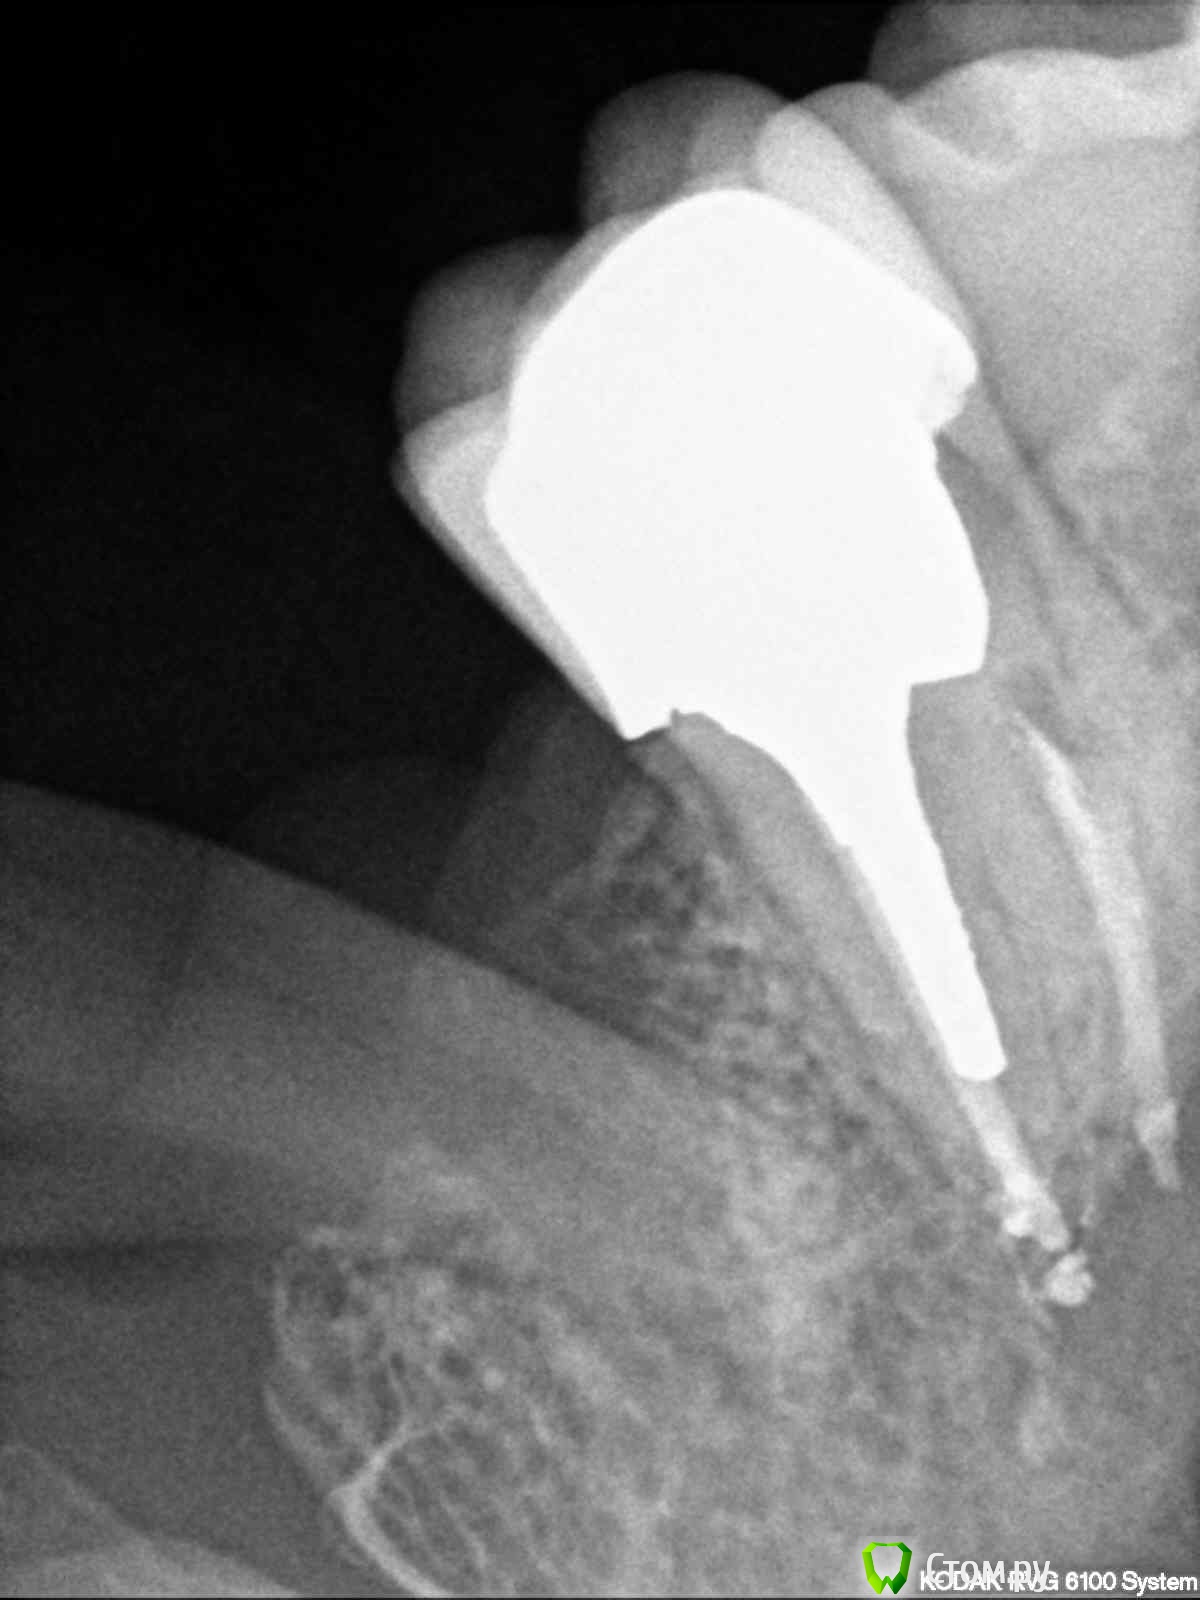

englishlady Опубликовано 3 декабря, 2013 Автор Поделиться Опубликовано 3 декабря, 2013 Спасибо Вам большое за ответы. С фотографиями, навеное, сейчас не получится. Если позволите, задам еще вопрос по 27 зубу. У меня на нем культевая вкладка и коронка. Он у меня стал не сильно ныть. На очном приеме в разных клиниках предположили, что это или из-за недавнего удаления 28 зуба или из-за 38 зуба, который находится в кости. Может быть проблема связана с вкладкой или коронкой, если это можно оценить по прицельному снимку. Снимок прилагаю. заранее спасибо за ответы. Ссылка на комментарий

englishlady Опубликовано 4 декабря, 2013 Автор Поделиться Опубликовано 4 декабря, 2013 Это снимки после пломбировки. Они совсем недавние. Каналы пломбировались прошлой зимой. Коронку одели летом. До октября-ноября зуб не беспокоил. Ссылка на комментарий